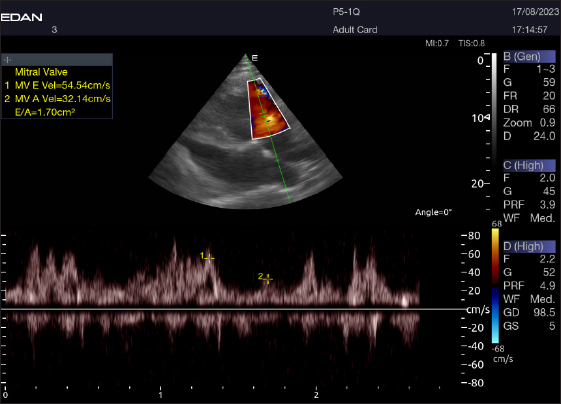

Table 4 provides an overview of pulsed-wave Doppler echocardiographic serial measures in adult racing camels. The pulsed-wave Doppler echocardiographic measurements’ mean values ± standard deviation were recorded for Tv E/A (1.3 ± 0.2 cm2), Mv E/A (1.3 ± 0.2 cm2), Av max (−88.2 ± 25.1 cm/second), and Pv max (−59.2467 ± 17.4 cm/second), as shown in Table 4.

The Mv E/A (Fig. 8), Tv E/A (Fig. 9), and maximum velocity of the aortic valve (Av Vmax) (Fig. 10) were all measured using pulsed-wave Doppler at LPSLAx in all camels. Two cases were observed with mild mitral regurgitation detected through continuous-wave Doppler, but the regurgitation was not considered significant (Fig. 11).

Fig. 8. Left parasternal longitudinal axis of a 16-year-old racing camel showing pulsed wave Doppler over the mitral valve (1=E wave and 2=A wave).